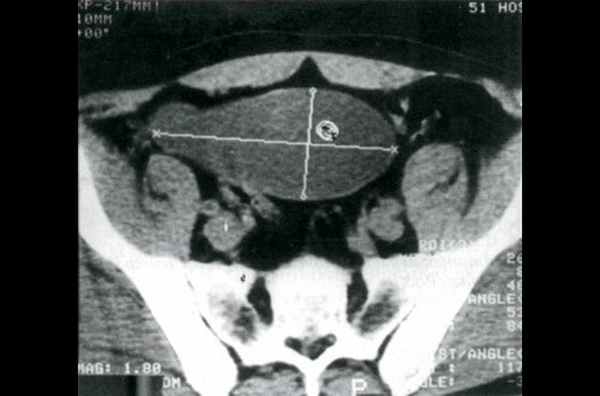

Больной К., 1936 г.р., поступил в абдоминальное отделение МРНЦ РАМН с предварительным диагнозом "новообразование брюшной полости". Жалоб нет, живот мягкий, симметричный. При пальпации в правой подвздошной области определяется объёмное образование диаметром до 10 см. Рентгенография органов грудной клетки - очаговых изменений не выявлено. Экскреторная урография: почки - без патологических образований, мочеточники расположены обычно, не расширены, мочевой пузырь правильной формы, с четкими контурами. Во время ирригоскопии патологических изменений в толстом кишечнике не выявлено.

Компьютерная томография органов брюшной полости до и после внутривенного введения 40 мл ультрависта: в правой подвздошной области определяется образование неправильной формы размером 12,4 х 5,9 см с ровными контурами, плотностью 33-35 ед, без изменения после введения контрастного вещества (рис. 1). Структура образования неоднородная, с наличием точечных и тяжистых включений, прослеживается тонкая капсула, местами утолщенная и уплотненная, с наличием кальцинации по задней стенке. Верхний полюс образования располагается в илеоцекальном углу, спереди оно прилежит к передней брюшной стенке, медиально - к сигмовидной кишке, сзади - к m.iliacus и правым общим подвздошным сосудам, внизу - спускается в виде ножки в малый таз, плотно прилегая к стенке прямой кишки и мочевого пузыря. Признаков поражения указанных органов не выявлено. Образование подвижно, при сравнении с данными ранее проведенного КТ-исследования отмечается изменение формы и положения. Увеличенных лимфатических узлов в подвздошной области и забрюшинно не выявлено.

Рис. 1. Мукоцеле червеобразного отростка. Компьютерная томограмма.